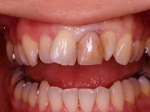

術後

インセラム(オールセラミック)冠による修復。 主訴は前歯が汚い 金属を使わないオールセラミックでの治療を勧めた。 術前